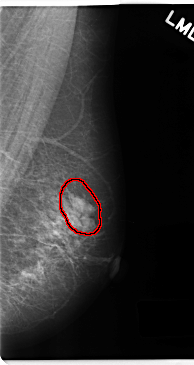

C_0186_1.LEFT_MLO

FILE: C_0186_1.LEFT_MLO.OVERLAY

TOTAL_ABNORMALITIES 1

ABNORMALITY 1

LESION_TYPE MASS SHAPE OVAL MARGINS CIRCUMSCRIBED

ASSESSMENT 4

SUBTLETY 5

PATHOLOGY BENIGN

TOTAL_OUTLINES 1

BOUNDARY